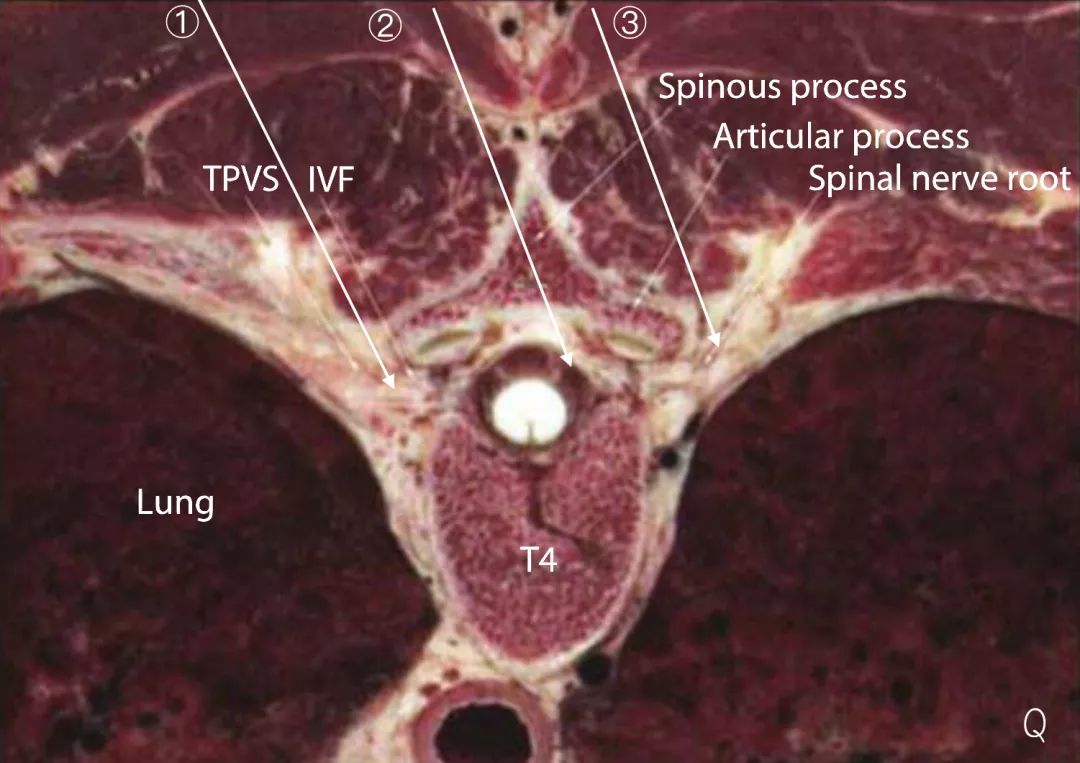

(TPVS:胸椎旁间隙,IVF:椎间孔,Spinous process:棘突,Articular process:关节突,Spinal nerve root:脊神经根)

上图①为IAP内向平面内入路,③为IAP外向平面内入路,②显示针尖穿透黄韧带进入椎管内。

但是,需要指出的是,在实际操作过程中,进针点旁开背部正中线,向外侧进针的同时,针体从头端向尾端也稍有倾斜,而胸椎椎板和棘突呈覆瓦状排列,如进针点正确、操作手法正确、患者解剖无畸形,笔者认为,针尖不会误入椎管。配合超声引导,注意神经阻滞针超声影像的识别,此入路不失为一条安全的入路。